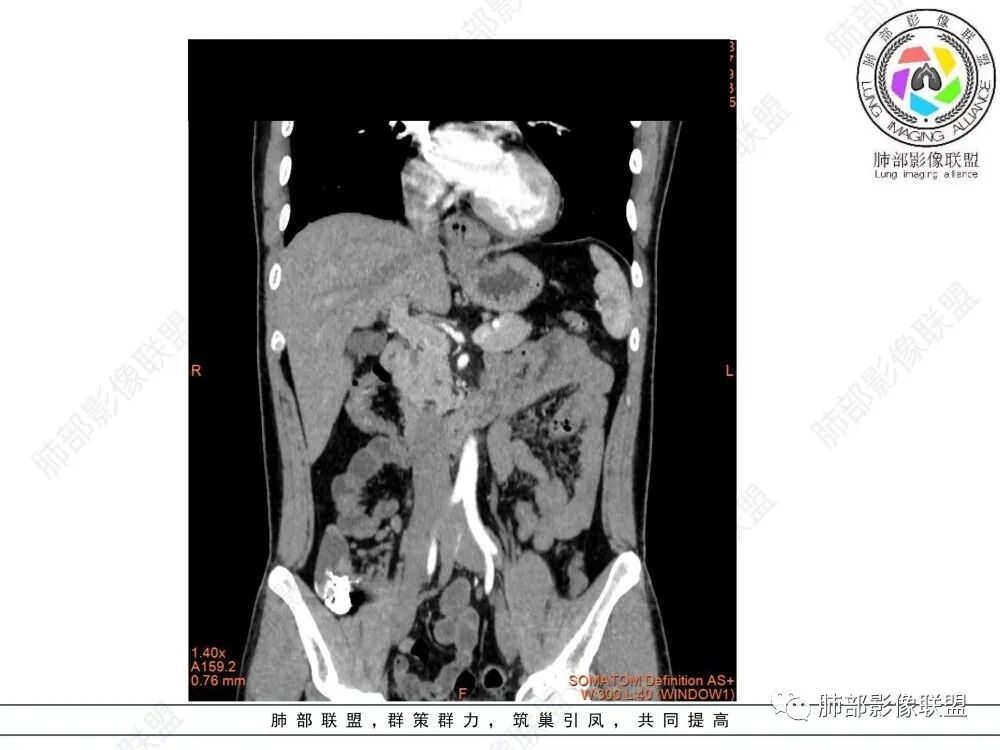

定位后纵膈,实性密度,增强轻度强化,T1等低信号T2低信号,弥散未受限。钡餐造影,食道及贲门管壁柔和,造影剂通过顺畅。考虑神经鞘瘤。鉴别食道平滑肌瘤。

后纵隔占位,质地均匀,信号中等,与食管关系密切,弧形受压,食管粘膜完整。考虑平滑肌瘤或孤立性纤维瘤。鉴别:神经源性肿瘤。

食管下段肿块,环壁生长,分叶状,密度比较均匀,钡餐造影食管下段弧形受压移位,并可见龛影,考虑为食管平滑肌瘤或食管结核。

后面造影图,像腔外  南边老师看得仔细

造影虽然像外压,但是ct肯定更清楚,看ct就是一个环绕管壁生长,管腔狭窄,定位应该没有问题,但是大家病理都答对了,太厉害了

食管平滑肌瘤是最常见的食管良性肿瘤,多见于男性,男女之比为2.6:1,高发年龄 30~60岁之间与食管癌相比,食管平滑肌瘤 的一个主要特点是病史相对较长,病情进展缓慢。病史最长者达10年余,平均 15.7个月,尽管病史较长,但大多数患者仍能进普食。食管平滑肌瘤的诊断一般比较容易,结合患者临床症状、食管造影及食管镜所见,一般均能得出正确诊断。食管造影主要为充盈缺损,病变与食管壁成锐角,粘膜线连续无破坏,管腔收缩扩张比较自如。钡餐造影敏感性高,但对食管壁间及食管周围情况难以判断。CT具有极高的密度分辨率,并且可以获得高质量的多平面重组图像,有利于食管壁间及食管周围情况的判断,表现为食管下段环绕管壁生长,偏心性或薄厚不均软组织密度肿块,密度均匀,内缘分叶状,管腔与正常食管壁构成不规则多角形扩张,增强动脉期无强化,多角度重建其病灶长轴与食管长轴不一致。由于食管壁在收缩状态下厚度约为5.6mm,扩张状态厚度不超过3mm,CT扫描时保持食管处于扩张状态可提高小病灶检出率。MR表现为T1加权等信号,T2加权稍高信号,可见高信号粘膜层,增强扫描轻度渐进性强化,密度均匀,无出血坏死。对于粘膜及周围脂肪间隙的判断具有明显优势。